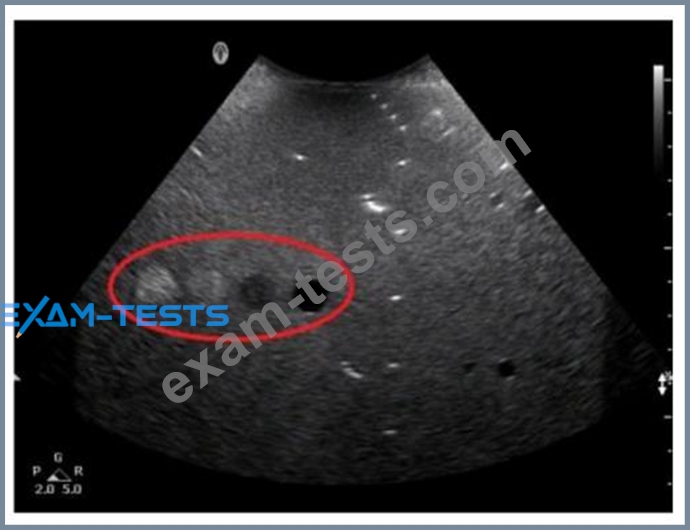

Which resolution can be evaluated in the area indicated by the red oval in this image of a tissue-equivalent phantom?